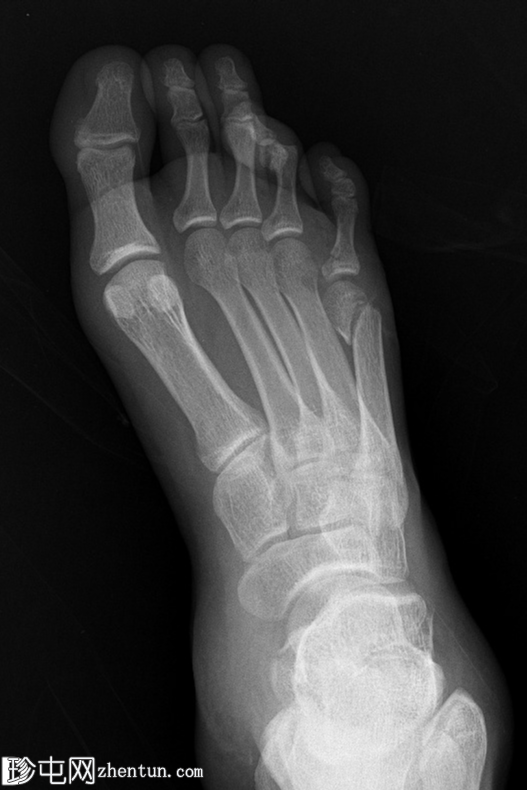

斜位

第四趾近节指间关节(PIPJ)跖侧脱位。

第五趾近节指骨无移位骨折。

第五跖骨颈骨折伴跖侧移位(背侧成角)。

跟骨关节内骨折。